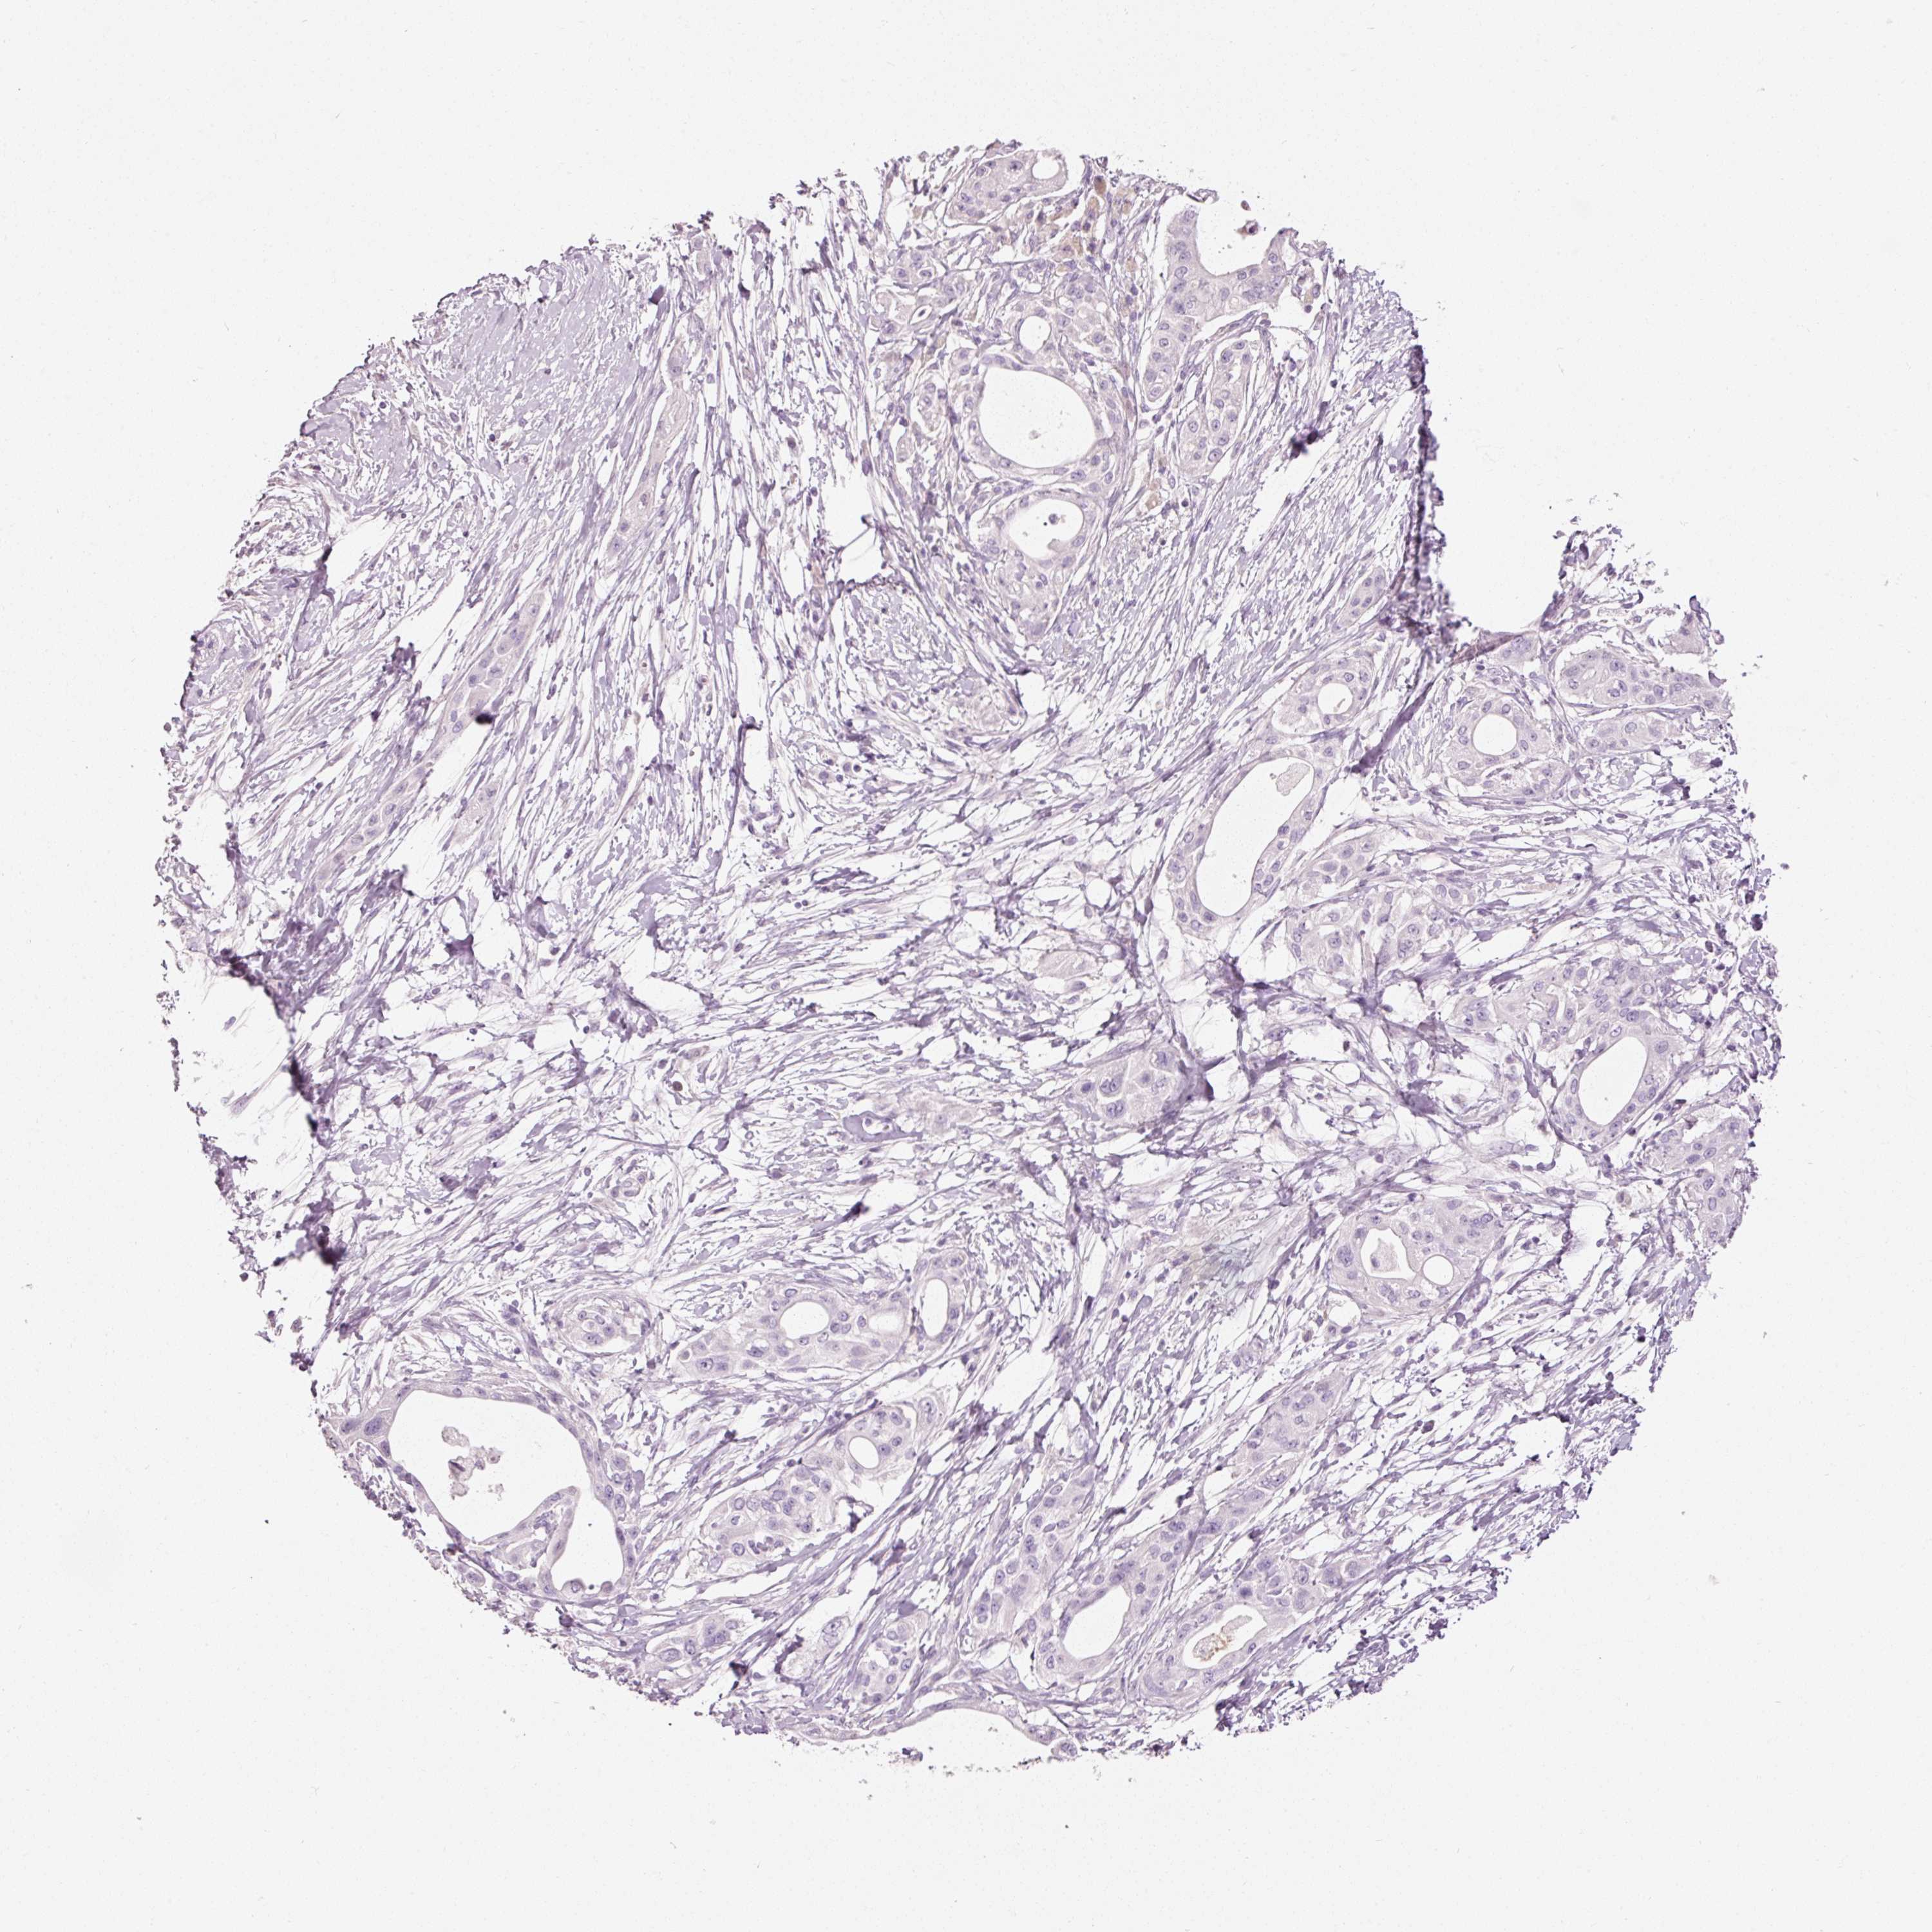

PANCREATIC CANCER - Protein expressioni

A mouse-over function shows sample information and annotation data. Click on an image to view it in a full screen mode. Samples can be filtered based on level of antibody staining by selecting one or several of the following categories: high, medium, low and not detected. The assay and annotation is described here.

Note that samples used for immunohistochemistry by the Human Protein Atlas do not correspond to samples in the TCGA dataset.

Antibody stainingi

Antibody staining in the annotated cell types in the current human tissue is reported as not detected, low, medium, or high, based on conventional immunohistochemistry profiling in selected tissues. This score is based on the combination of the staining intensity and fraction of stained cells.

Each image is clickable and will lead to virtual microscopy that enables deeper exploration of all samples and also displays staining intensity scores, fraction scores and subcellular localization as well as patient and tissue information for each sample.

Adenocarcinoma, NOS

Adenocarcinoma, metastatic, NOS